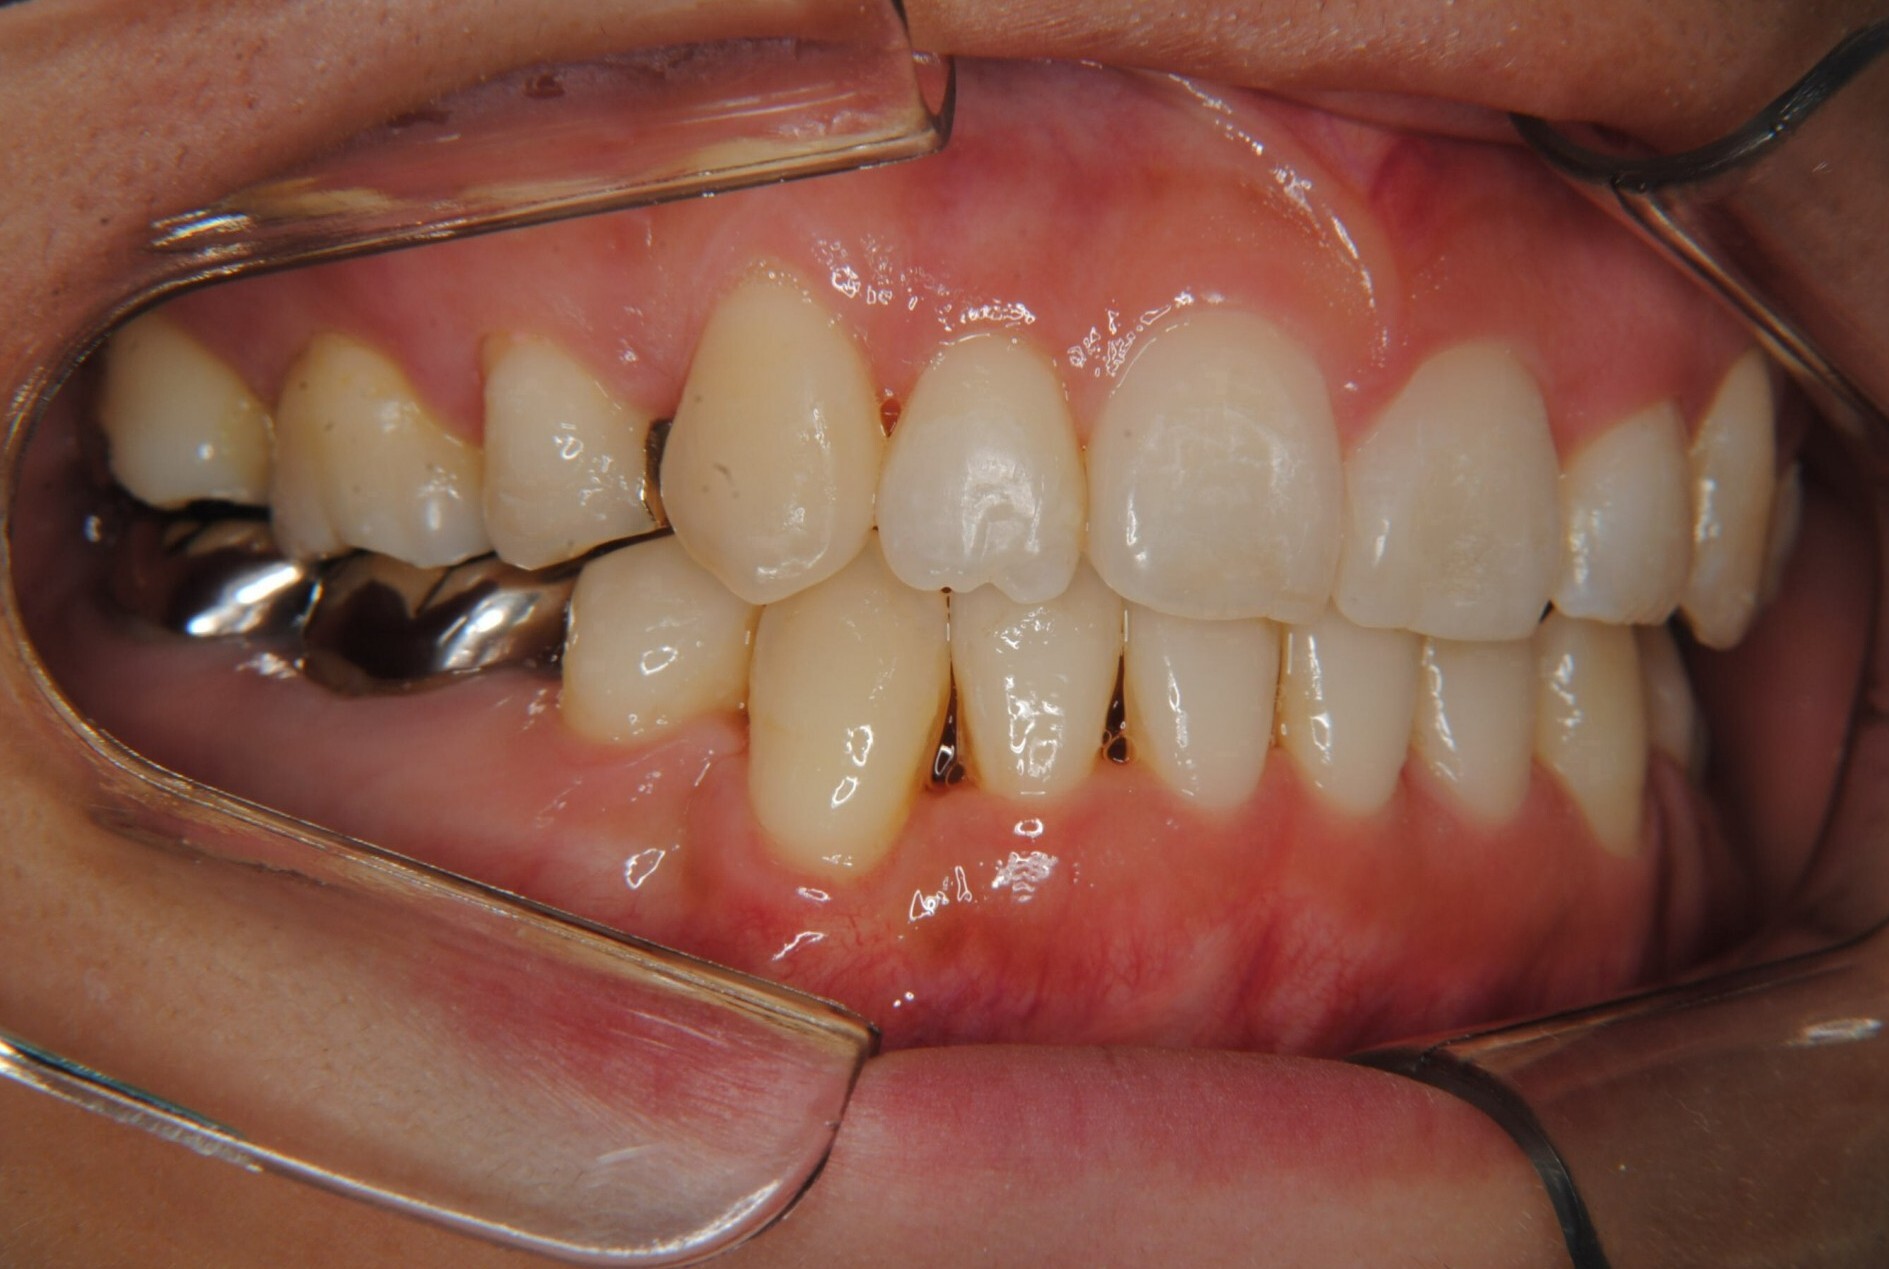

⑧リスクと副作用:マルチブラケット装置(T21ブラケット)を初めてつけてから4日間、食事の時におもに前歯が少し痛かったとのことでした。治療後のエックス線写真で、歯根吸収はほとんど観察されず、歯肉を診ると残念ながら下顎前歯部に歯肉退縮(ブラックトライアングル)が生じていました。しかし、通常下顎前歯部は下唇に隠れてむき出しにはなっていないので、ご本人はあまり気にされていないご様子でホッとしています。